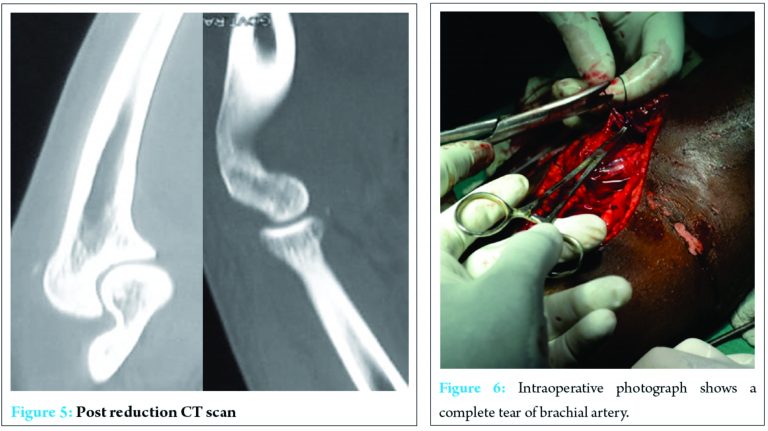

Closed reduction was done under intravenous sedation in the minor operating room, and the elbow joint was found to be stable post reduction. The reduction maneuver being traction at wrist and counter traction at the arm, mild flexion and posterior displacement of forearm. The postreduction radiograph (Fig. 4) and computed tomography (Fig. 5) showed congruent reduction. This was done immediately following closed reduction. As there was severe swelling and the distal vascularity insufficient, an attempt of closed reduction was done before the vascular surgeon assessed the limb vascularity, in the idea to reduce the ischemia time and that the compression of the neurovascular structures by the dislocated bony parts, could be temporarily relieved by closed reduction of the elbow joint before contemplating over open reduction or any vascular procedure.

After reduction, radial pulse was still absent and vascular surgeon assessment revealed clinically absent distal pulses but monophasic flow in radial artery on a hand-held Doppler probe showing no significant improvement in the vascularity of the limb even after closed reduction. A primary exploration of the brachial artery was planned. Intraoperatively, the brachial artery was found to be lacerated (Fig. 6). Long saphenous vein was harvested from the ipsilateral leg and used as a bypass graft at the injured level of brachial artery. The posterior interosseous nerve was found to be intact but with a minimal contusion. In addition, a prophylactic fasciotomy (Fig. 7) of the forearm was done.